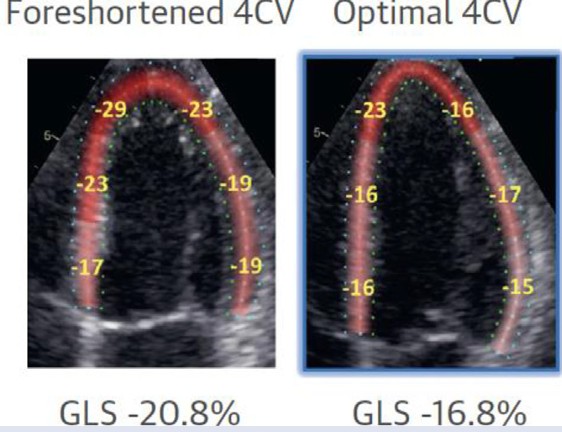

(1) Evitar uma janela apical encurtada, pois desta forma haverá um aumento não verdadeiro dos valores do strain nos segmentos apicais. Desta forma, é preciso garantir que o ápex verdadeiro esteja sendo visualizado.